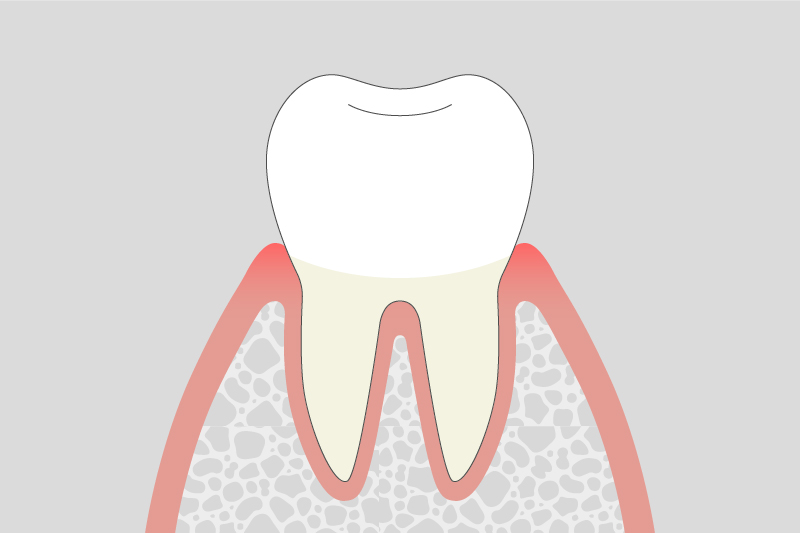

01.

歯肉炎(極軽度の歯周病)

歯ぐきが赤く腫れ、出血しやすくなる。